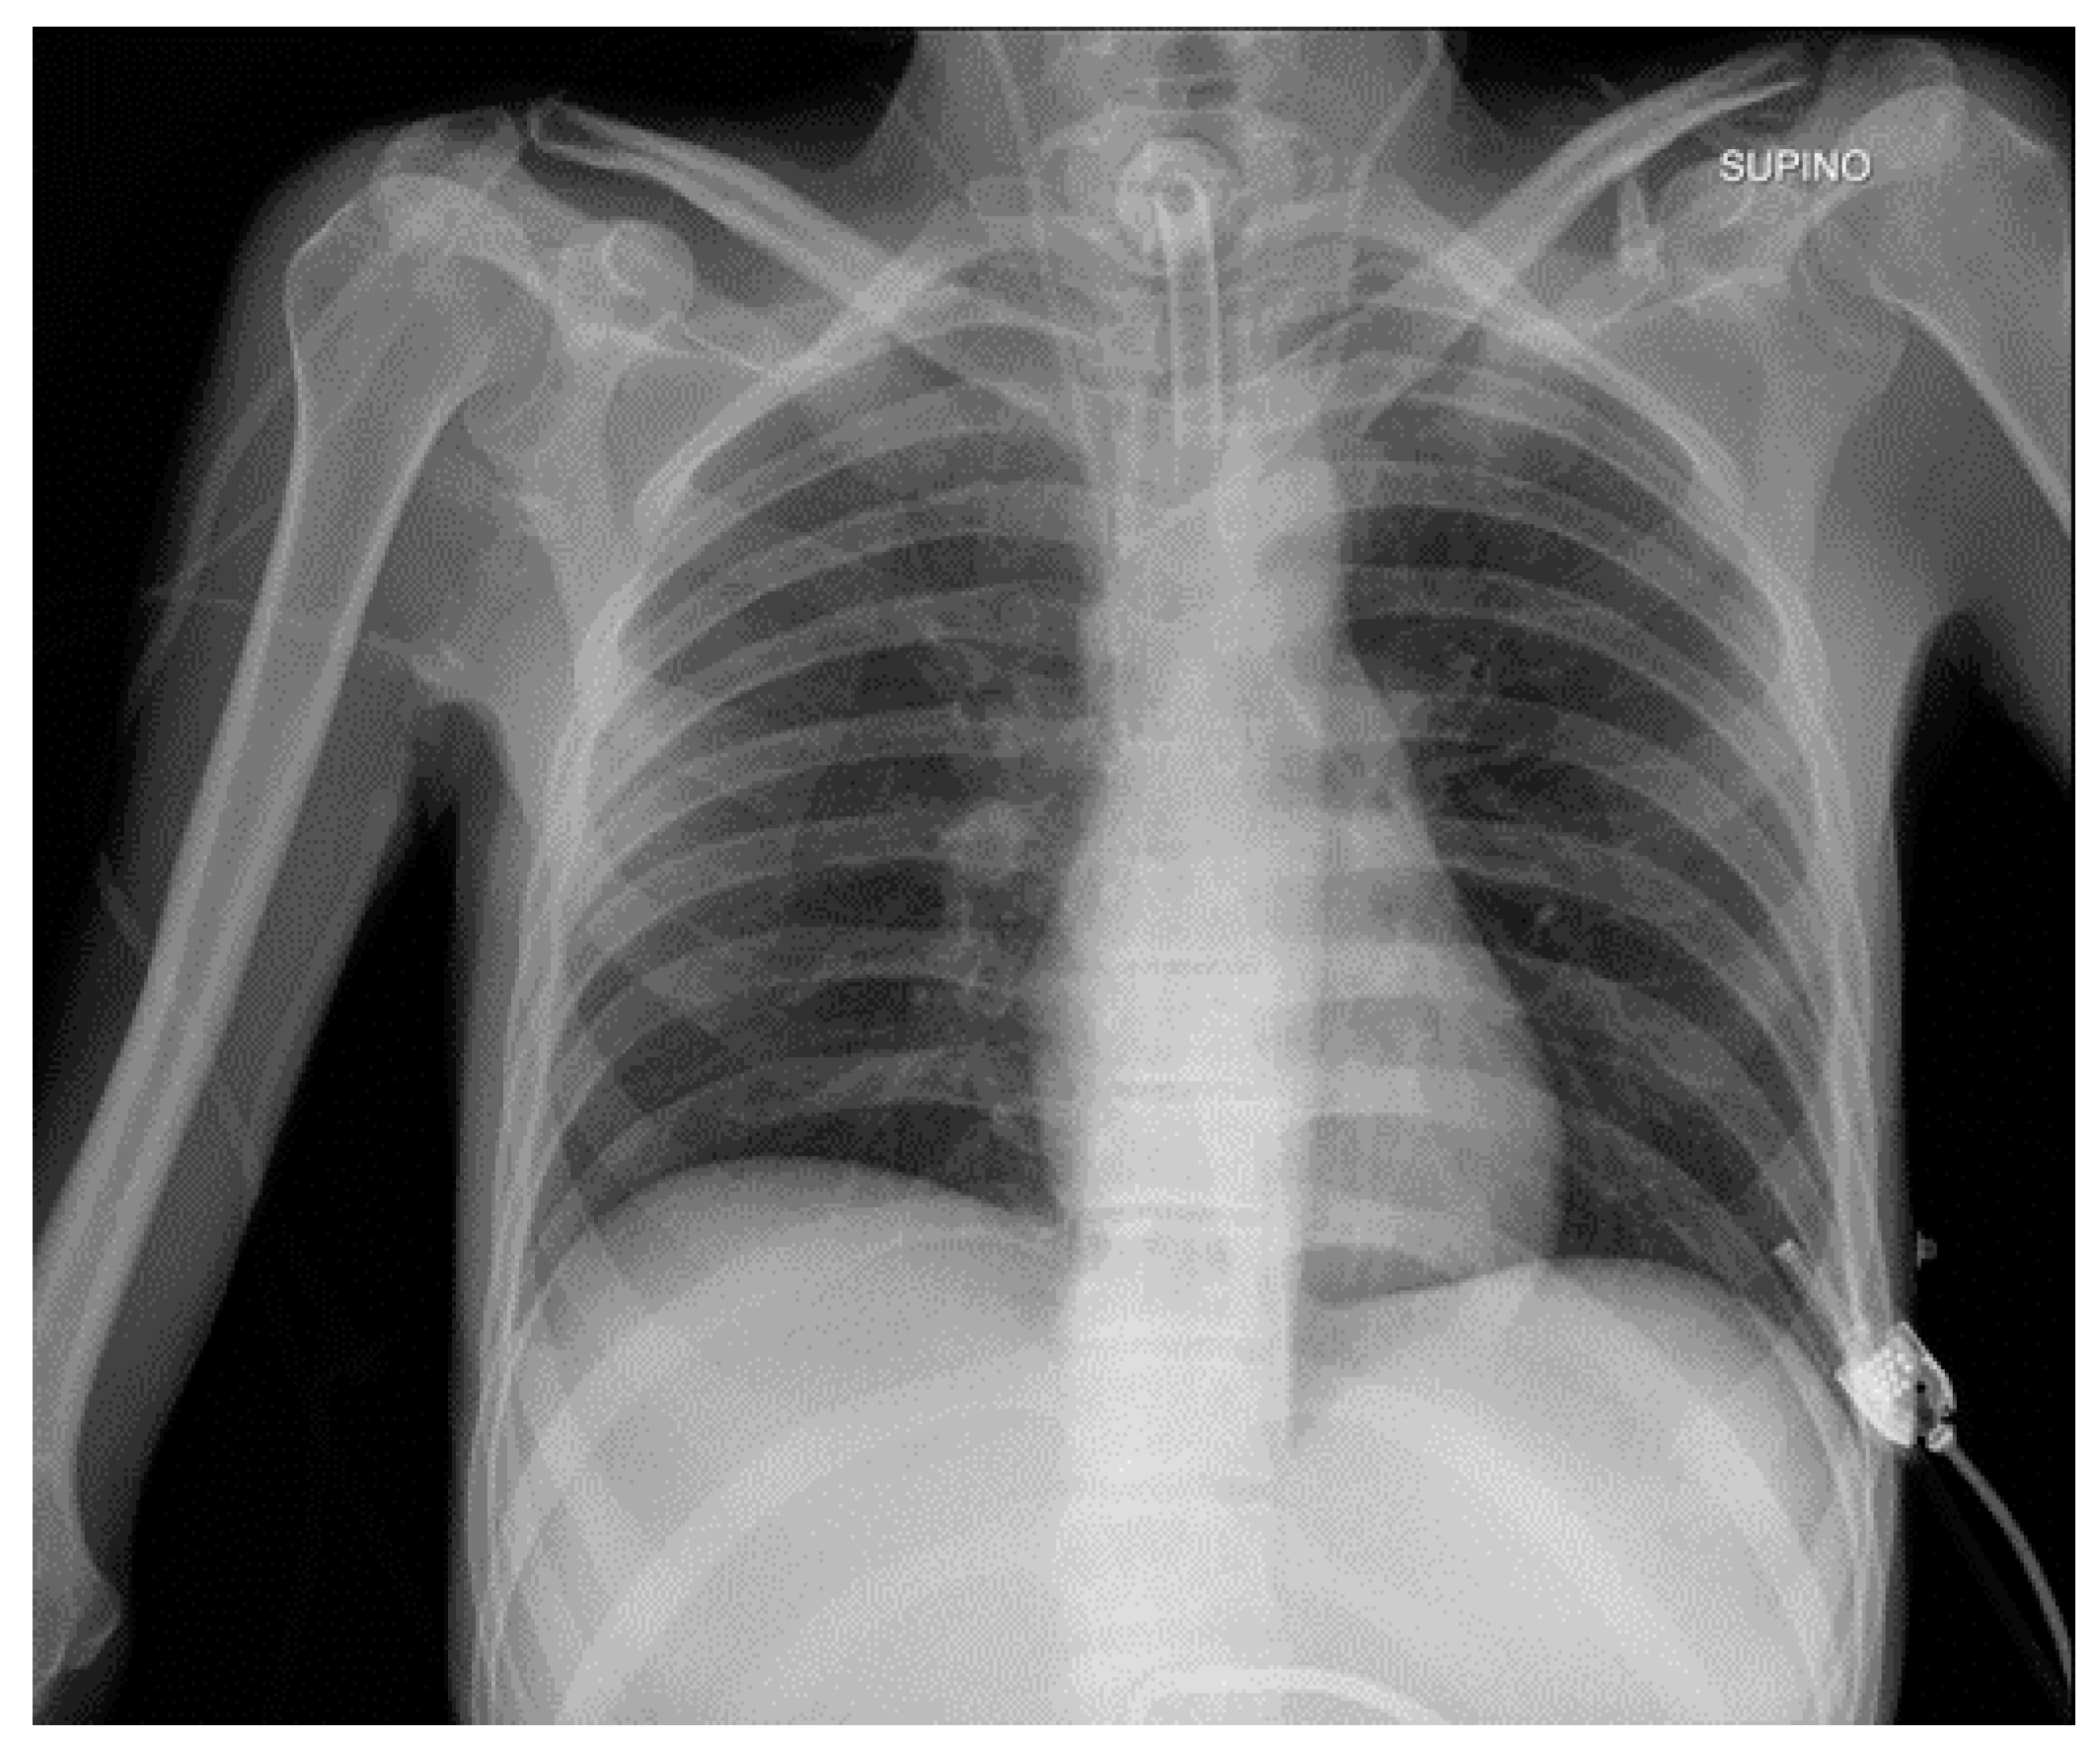

Potential confounding factors are EKGs’ leads, external tubes, artifacts and overlapping of different devices. The need to have at least two orthogonal projections to correctly locate a device can be a limit in patients in which only an anteroposterior projection is feasible. Moreover, technical factors must be considered, such as the orientation of the X-ray tube and patient rotation (Figure 1) [2].

Figure 1.

Potential confounding factors when checking for devices on a CXR. (a) Anteroposterior CXR of a right-sided rotated patient can simulate the dislocation of the central venous catheter (white arrows). (b) Anteroposterior CXR of a patient with multiple devices and external EKG leads.